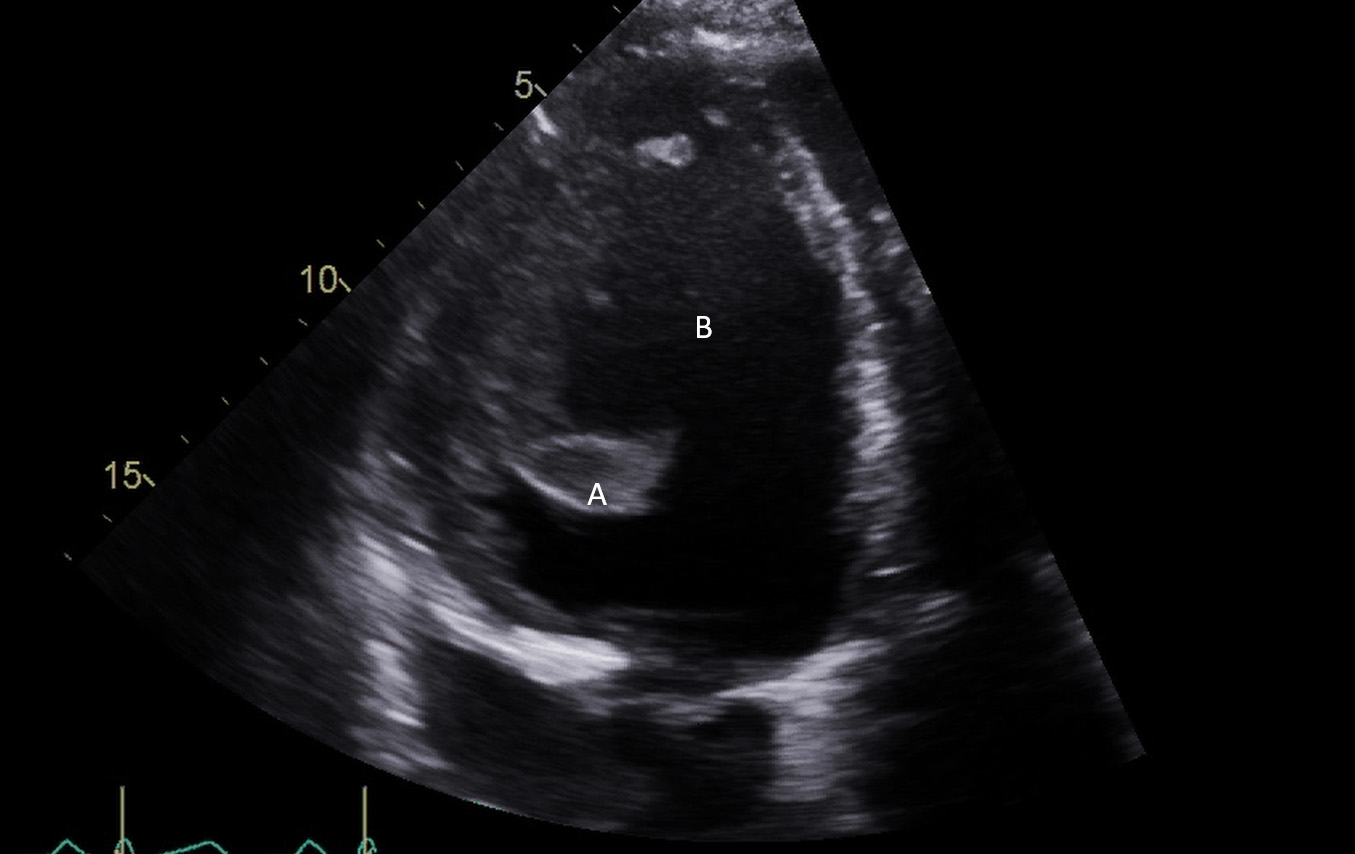

Both TTE and TEE can help with ideal positioning of the Impella (Figs. 5,6). The distance from the aortic valve to the Impella inlet should be measured. This should ideally be 3.5–4 cm for all Impella devices except for the Impella 5.5 for which it is 5 cm [15] (Fig. 7). The outlet should be 1.5–2 cm above the sinuses of Valsalva. The catheter should be angled towards the LV apex and away from the septum and mitral valve. The positioning of both the inlet in the LV cavity and the outlet above the aortic valve should be confirmed. Color flow doppler imaging can help confirm this positioning as a mosaic pattern will be visualized near the inlet and outlet ports on spectral doppler (Fig. 8). Real-time 3D echocardiography can also be used to help in visualizing Impella positioning relative to other anatomical structures (Fig. 9). After placement of the Impella, the aortic and mitral valves should be interrogated for any new or worsening regurgitation or dysfunction [16]. TEE can also help identify additional complications of Impella placement including pericardial effusion or LV free wall rupture [17].

Fig. 7.A parasternal long axis view on a transthoracic echocardiogram. The distance from the Impella inlet to the aortic valve is measured and noted to be 3.9 cm. (A) LV Cavity. (B) Impella. (C) Ascending aortic root.